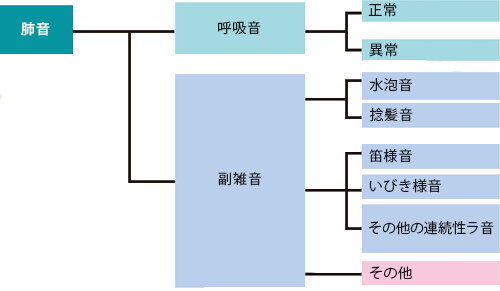

肺音分類

American Thoraci Society と三上理一郎らによる肺音の分類(「ラ音の分類と命名」日本医師会雑誌94(12):2050-2055, 1985)を習得することを目標としています。